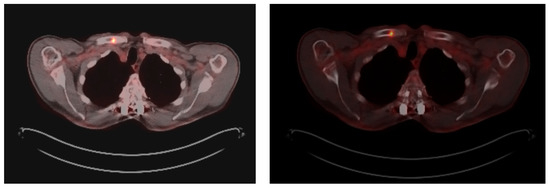

Furthermore, in November, a follow-up PET/CT shows the metabolic progression of the same lytic lesion since the relapse with SUVmax = 19, currently with the associated pathological fracture supporting the progressive myeloproliferative disease (Figure 4).

Figure 4. Progression of hypermetabolic lytic lesion (SUVmax = 19) in the medial third of the right clavicle four months after the previous one.